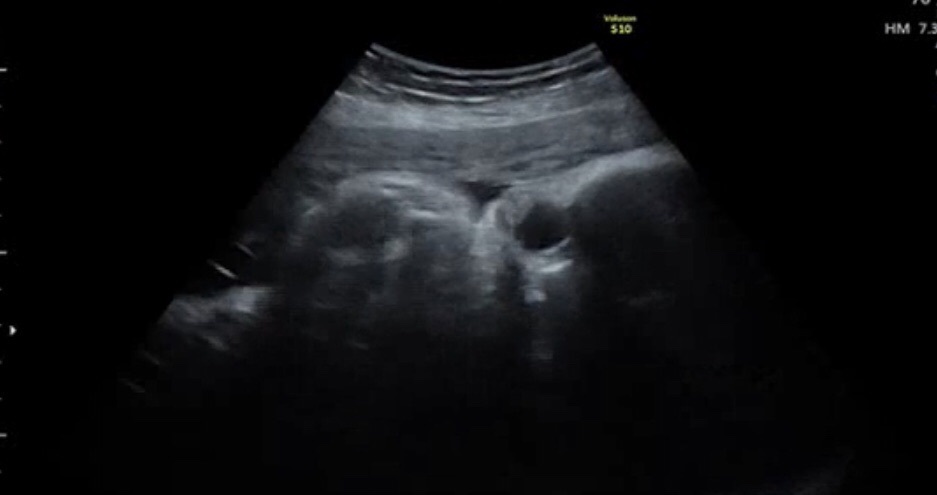

エコー

最近 、エコーで お顔を見ると

子宮の壁に 顔を押し付けてて 、

顔がぐちゃってなってて 心配になる 🤭 💬

おっきくなって だいぶスペースが

無くなってきてるんだろうなぁ 。

4Dでみても 、顔がよく分からないくらいに

窮屈そうにしてるけど 大丈夫なのかな ? 🤥